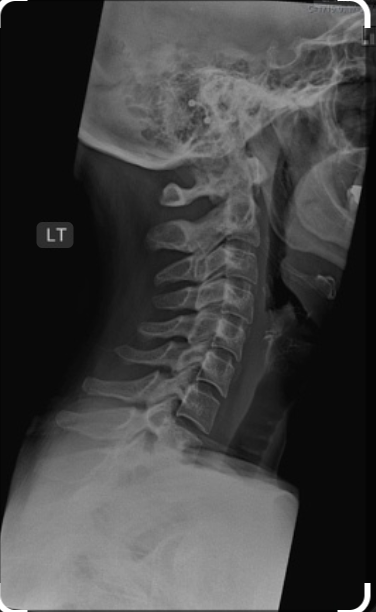

X-ray Cervical Lateral

Medifyhome provides X-ray Cervical Lateral is available at affordable prices. An X-ray Cervical Lateral is a diagnostic imaging procedure that provides a side view of the cervical spine, encompassing the seven vertebrae (C1–C7) in the neck region. This type of X-ray is primarily used to evaluate the alignment, structure, and overall health of the cervical spine. The lateral view allows healthcare providers to visualize the vertebrae, intervertebral spaces, and surrounding soft tissues, making it a valuable tool for diagnosing issues like whiplash, osteoarthritis, disc space narrowing, or bone spurs.

It is a quick, non-invasive, and cost-effective method, making it a first-line diagnostic tool. It is particularly useful in assessing conditions such as trauma, fractures, dislocations, degenerative changes, and abnormalities in the spinal curvature, such as cervical lordosis. While the radiation exposure is minimal, it is still a consideration for certain patients. To book an X-ray Cervical Lateral with Medifyhome, visit our website or call us at +919100907036 or +919100907622. Experience hassle-free, reliable, and affordable medical imaging services tailored to your needs. Trust Medifyhome for accurate diagnostics and a seamless healthcare experience.

An X-ray Cervical Lateral (Lateral View of the Cervical Spine) is an X-ray imaging test that captures a side (lateral) view of the cervical spine (neck region). It helps assess the alignment, structure, and possible abnormalities in the vertebrae (C1-C7), intervertebral discs, and soft tissues of the neck.